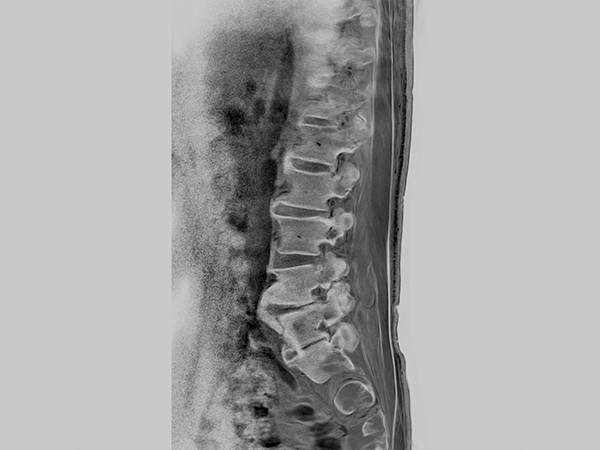

Sagittal CWI FFE